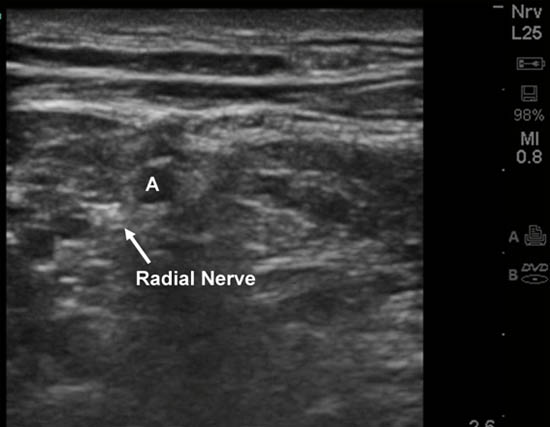

The ideal location for finding the radial nerve without ultrasound guidance is at the elbow. With ultrasound guidance the nerve is visible deep to the brachioradialis muscle. The radial nerve may be difficult to follow distally from the elbow, and at best only the superficial branch can be visualized.[3] One injection at this site may block both the deep and superficial branches of the radial nerve (Figure 4).

Figure 4. Ultrasound-guided radial nerve blockade in the forearm.